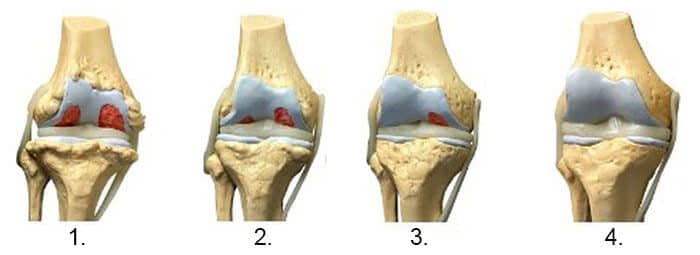

1. Nedostatak zajedničke prehrane. Tkiva niti su uništena.

2. Regeneracija tkiva zglobne hrskavice nakon dva tjedna korištenja "Osteon".

3. Regeneracija tkiva zglobne hrskavice nakon 3 tjedna korištenja "Osteon".

4. Zdrav zglob nakon završetka liječenja s Osteon.

-Donja rendgenska slika prikazuje tipičan obrazac regeneracije zgloba koljena.